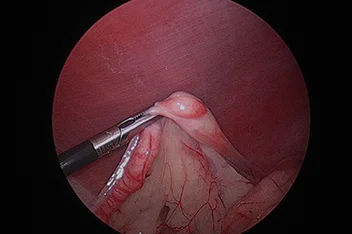

관절경

개,고양이 들은 다양한 관절질환이 존재하고, 복합적으로 존재하는 경우도 빈번합니다.

정확한 진단이 나지 않은 뒤 수술을 하게되면 증상개선이 더디거나 개선이 안될 수 있어, 정확한 진단이 필요합니다.

관절의 경우 X-ray 촬영등으로 진단의 한계가 명확하며, 상위 검사인 CT, MRI 촬영으로도 진단의 한계가 있습니다.

이때 관절경은 내부 구조물들을 직접 시각화 하여 보다 정확한 관절의 상태를 확인하고 진단할 수 있으며, 진단과 치료를 동시에 진행하는 경우도 있습니다. 대표적으로 십자인대단열(CCLR), 골연골염(OCD), 자뼈꿈치돌치유합부전(UAP), 내측관상돌기질환(MCD) 등에 활용될 수있습니다.

관절경 팔꿈치관절(Elbow) 확인

관절경 무릎관절(Stifle) 확인 (반월판 및 십자인대)

* 리본동물의료센터 케이스 사진으로 무단 복제 및 도용을 금지합니다.